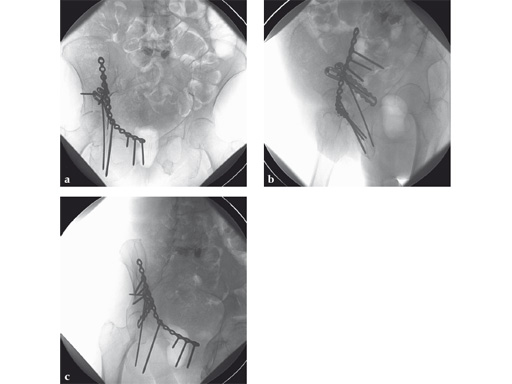

Fig 3ab AP hip and iliac oblique image intensifier views show initial quadrilateral surface plate placement with the aid of an asymmetrical clamp and subsequent introduction of overlying pelvic brim reconstruction plate. In this case a locking pelvic brim plate was chosen because of the severe osteoporosis.